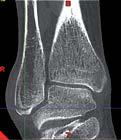

Nell’ambito della radiologia 3D ortopedica, il centro diagnostico utilizza il nuovissimo macchinario NewTom 5G XL, in grado di individuare con la massima precisione la presenza di fratture o lussazioni delle articolazioni, controllare la corretta guarigione di una frattura, valutare una lesione o una ferita causata da infezione, artrite o crescita anormale dell’osso.

Il tutto mediante una semplice e veloce scansione, grazie alla quale si otterranno diverse immagini in 3D ad altissima risoluzione e, per ottenere immagini ancora più nitide mediante un bassissimo dosaggio di radiazioni, gli esperti si avvalgono dell’innovazione racchiusa nella tecnologia Cone Beam.

Se con la radiologia tradizionale era necessario eseguire scansioni multiple, la novità introdotta dal macchinario NewTom 5G XL risiede nella capacità di fornire immagini ad alta risoluzione in un’unica scansione, mostrando nitidamente i dettagli delle articolazioni degli arti superiori e inferiori. Inoltre, a differenza della tecnologia 2D, la radiologia 3D ortopedica permette di individuare immediatamente alcune patologie come quella del metatarso, la quale richiede un allineamento visivo dedicato o una diagnosi delle micro fratture ossee.